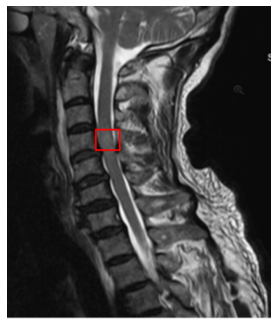

Typically, when spinal injuries involve the spinal cord, they can manifest as various degrees of signal changes. MRI can not only observe the morphological changes of acute SCI but can also precisely determine the degree of SCI based on changes in the spinal cord signal. Moreover, it can detect occult fractures and spinal cord edema, which significantly guides the formulation of treatment plans and the determination of prognosis. The MRI manifestations of SCI vary according to different lesion presentations. We consulted relevant literature on the MRI of SCI [20-22] and sought advice from professional spinal surgeons regarding its classification, finding two main types: one is based on the cause of injury, using cervical SCI as an example, which can be divided into Types I-IV, as shown in Figure 1 and Table 1; another classification method is based on the pathological changes in the spinal cord tissue, mainly divided into hemorrhage, edema, mixed type, etc., as shown in Table 2. From a medical professional perspective, the cause of injury in the first classification ultimately leads to pathological changes in the spinal cord that follow. For instance, cystic changes and glial scar formation, such types of pathological changes, usually occur during the recovery period, with early manifestations primarily being hemorrhage, edema, and mixed type. Therefore, this paper mainly uses the second classification method to detect the types of signal abnormalities in MRI and summarizes the characteristics of signal changes in SCI on MRI as shown in Table 2.

Figure 1. Imaging classification of acute cervical SCI (based on cause of injury)

Table 1. Imaging classification of acute cervical SCI (based on cause of injury)